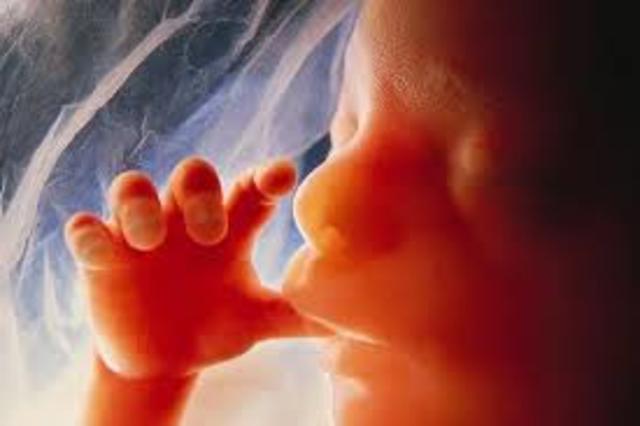

The fetus now actually looks like a baby and not like an alien. The increaded heartbeat, 160 bpm, results from the baby moving around, but you still cannot feel it.

Although your baby has it's hands, their nerve connections are still devloping as they explore themselves and your uterus. If one day, daddy want to talk to peanut, theres a higher chance that the baby will hear them better than you.

The baby is very active in the womb and did you know that thumb sucking calms your child and tightens the jaw? So dont yell at kids that arent your kids to stop sucking their thumbs. Their brain is still developing and he can open his eyes now!